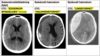

Apopleksi (stroke) og TCI (transitorisk cerebral iskæmi): **Definition**: pludseligt indsættende fokale neurologiske udfald forårsaget af forstyrrelser i hjernens blodcirkulation … - **TCI**: < 24 timer - **Apopleksi**: > 24 timer Årsag: - Infarkt - **Iskæmisk apopleksi (80-85%)** - Hjerneblødning - **Hæmoragisk apopleksi (10-15%)** Udredning og Diagnose: **CT cerebrum (CTC)** **Behandling**: **1**

1: **Akut behandling**: - **Iskæmisk apopleksi/TCI**: trombolyse (Alteplase), evt. trombektomi - **Hæmoragisk apopleksi**: symptomatisk behandling og evt. kirurgisk behandling **Sekundær profylakse**: 1.valg: Clopidogrel 75 mg x1; KRAM-faktorer, etc. Tidsvindu for trombolyse: < 4,5 t (evt. op til 9 t med billeddiagnostik) Tidsvindu for trombektomi: < 6 t (evt. op til 24 t med billeddiagnostik)